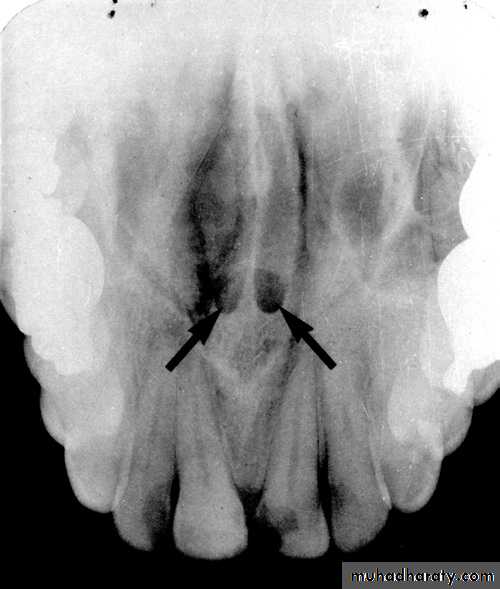

The genial tubercle are tiny bumps of bone that serve as the attachment sites for the genioglossus and geniohyoid muscles, its located on lingual aspect of the mandible. On mandible periapical radiograph the genial tubercle appears as a ring shaped radiopacity below the apices of the mandibular incisor.

LINGUAL FORAMEN

:

The lingual foramen is a tiny opening or hole in the bone located on the internal surface of mandible, its located near the midline and surrounded by genial tubercle. Radiographically, the lingual foramen appears as small radiolucent dot located inferior to the apices of mandibular incisor.